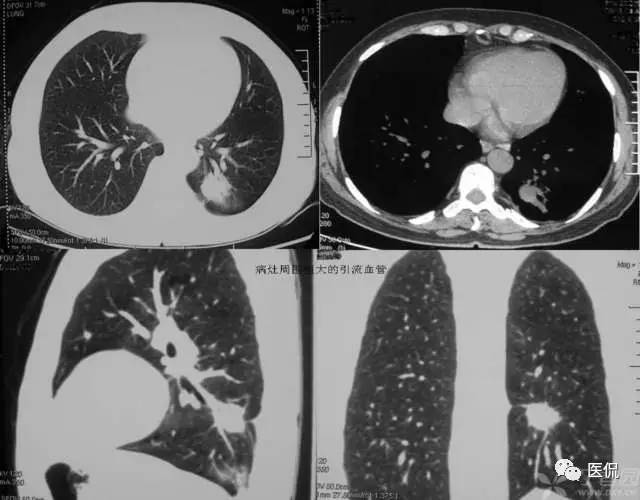

磨玻璃密度(GGO)

胸部影像上表现为肺密度的轻度增加,透过这种磨玻璃影像可以看到肺纹理的影像。该征象包括下属几种情形:1)弥漫型 如严重的急性肺移植排斥反应、早期成人呼吸窘迫综合症、肺水肿、过敏性肺炎、肺出血、各种原因的感染如非典型性肺炎等;2)斑片型 如各种类型的肺炎、肺泡蛋白沉积征、类脂质肺炎、卡氏肺囊虫病以及成人呼吸窘迫综合症等;3)局灶型 肿瘤如肺炎型肺泡癌、肺外伤、肺梗死等,这种类型常常和上述两种的病因相重叠;4)晕型 常见于早期浸袭性肺曲霉菌病,也可见于肺穿刺之后;5)支气管血管型和小叶中心型 如嗜酸性肺炎、结节病、外源性过敏性肺炎、呼吸系支气管炎等,其间前二者多见于支气管血管型,后二者多见于小叶中心型。

磨玻璃征要根据病史探求病因,如患者有出血倾向而查不出其他原因时要考虑肺出血;患者有过敏体质,又有花粉吸入或有其他过敏原接触史要考虑外源性过敏性肺炎;有多系统病变的患者要考虑结缔组织性肺炎等等。

磨玻璃影的分布对于鉴别诊断也有帮助:1)呈小叶中心分布时,一般多是早期病变,常为支气管播散,可能是过敏性肺炎或脱屑性间质性肺炎所致;2)呈全小叶分布时,病变边缘清楚;呈部分小叶受累时,病变边缘模糊。前者可见于肺泡蛋白沉积征、药物中毒性肺炎、类脂质肺炎、肺结节病、卡氏肺囊虫病、肺炎吸收期间以及肺出血等;3)呈小叶周围性分布时,多为早期特发性肺纤维化的表现。

1)肺腺癌:

2)含铁血黄素沉着症:

3)特发性肺间质纤维化: